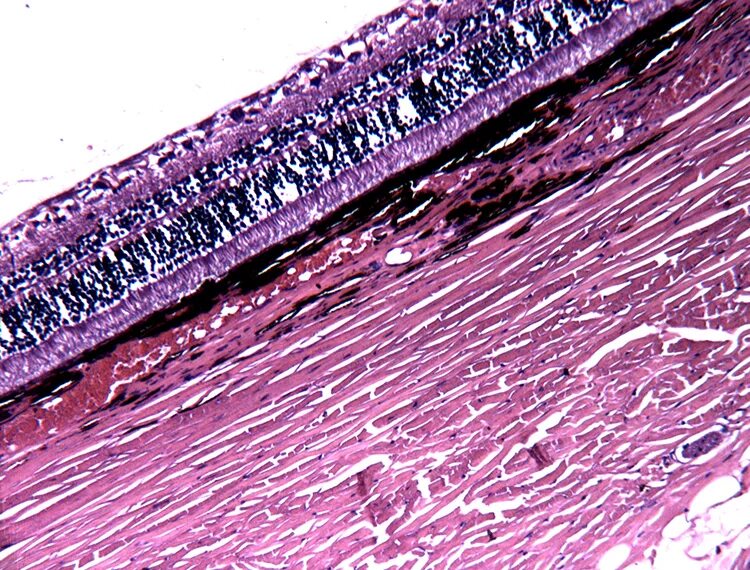

Гистологический срез это